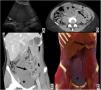

Radiología Abdomen agudo secundario a torsión de bazo errante

Abdomen agudo secundario a torsión de bazo errante

Acute abdomen secondary to torsion of a wandering spleen